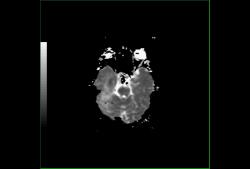

Диффузионная ADC карта